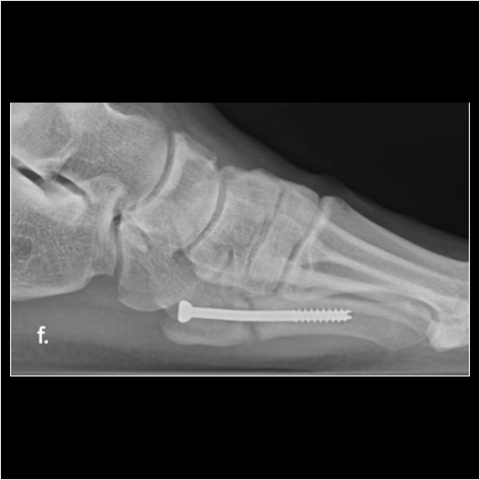

Figure 3f

Figure 3f. Here is the 28-year-old’s foot at 3 months.